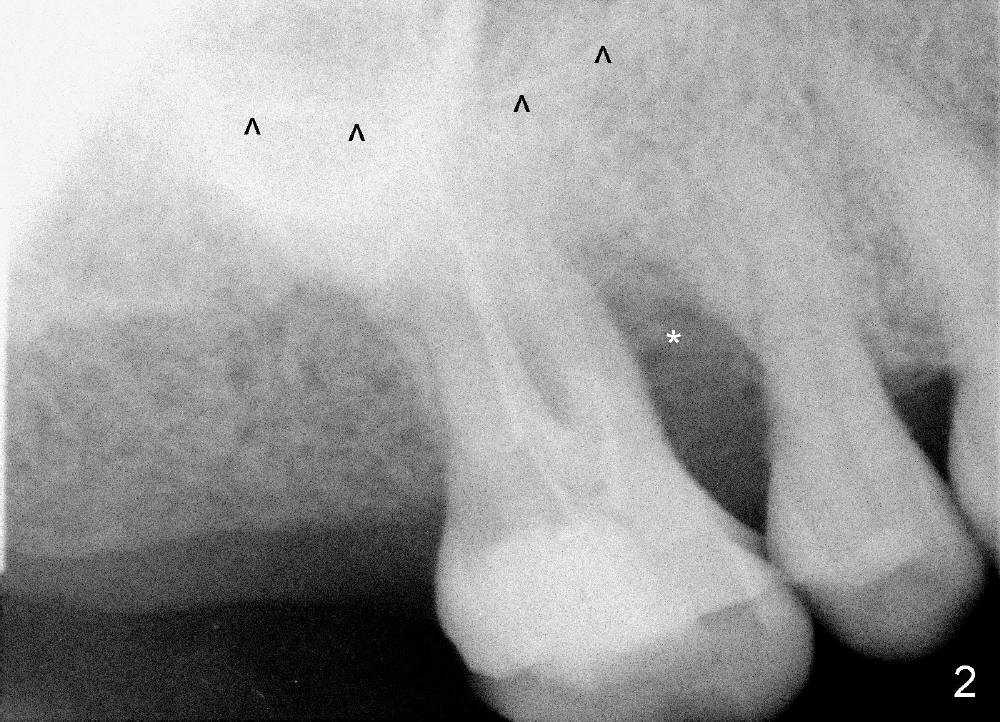

The upper right 1st molar fractures, the lingual portion mobile (Fig.1). There are deep pockets mesiolingually and distolingually. Fig.2 is preop PA, showing mesial bone resorption (*). The 84-year-old lady agrees extraction and immediate implant. Extraction is difficult due to not only root fracture but also hemorrhage. Following debridement of granulation tissue, the 3 sockets are packed with gauze for hemostasis. Even so, there is oozing from the bone. The septum can not be seen clearly. Its position is determined by an explorer. Osteotomes have to be used for osteotomy in the septum, followed by taps. The first intraop PA shows that 5x20 mm tap penetrates the sinus floor (Fig.3 ^). The osteotomy is further enlarged until 7x17 mm tap with stability (Fig.4). So far there has been no sign of sinus membrane perforation. Mixture of freeze dry mineralized bone and Osteogen is placed in the socket and pushed to the buccal and lingual walls as well as into sinus using a 4 mm flat end osteotome. A 7x17 mm implant is initially difficult to be inserted possibly due to blockage by bone graft. The osteotomy have to be recreated by a series of osteotomes and taps before placement of the 7x17 mm implant. It appears that the apical threads have been engaged into the sinus floor for primary stability (Fig.5). The insertion torque is 40 Ncm. According to our experience (1,2), this is not enough; finally the torque is increased to 60 Ncm by turning the implant more apically. The large implant obliterates the socket mesiodistally; the buccal and lingual gaps are filled with bone graft, followed by a collagen membrane (Fig.6 *) and suture. In order to protect the membrane, a short abutment is placed (A) and perio dressing (Fig.7*) is placed without occlusal interference. The abutment is removed 1 month postop, as the perio dressing has been dislodged. The patient returns for restoration 8 month postop. Bone regeneration occurs apparently in the coronal aspect of the implant (Fig.8), especially mesially (*, as compared to Fig.5). The gingiva-level implant is slightly subgingival mesially (Fig.9 M), probably due to high placement (compare to Fig.6). There is no bone resorption 6 months post crown (Fig.10 C) cementation.